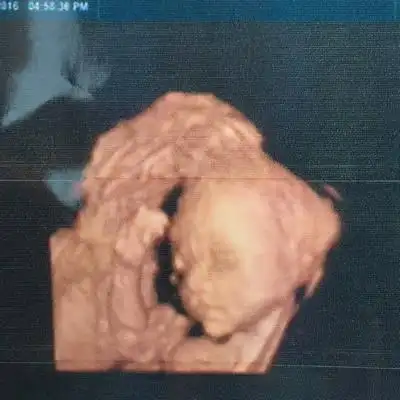

四维照片宝宝这样算兔唇吗

胎儿双侧唇裂四维成像图

大家帮忙看一下是兔唇吗?

昨天照了四维说唇腭裂好担心,不知道该怎麼办

双胎宝妈21周做四维彩超筛查出一名胎儿为唇腭裂